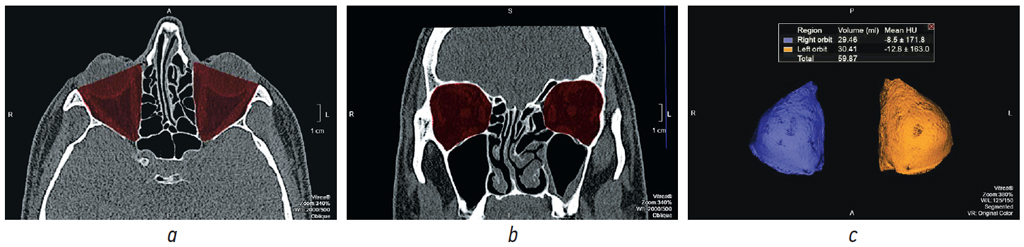

КТ-исследование лицевого скелета проводили на аппарате Aquilion One 640 по стандартной методике. Голову пациента укладывали на головную подставку, фиксировали центрально, использовали лазерные метки для определения уровней томографирования, получали изображения с толщиной среза не более 0,5 мм, с реконструкциями в костном и мягкотканном режимах. После КТ на полученных изображениях определяли костные границы орбит, по которым проходила маркировка стенок орбит. Необходимым условием правильного выполнения исследования являлась симметричность костных границ для обеих орбит. Для этого необходимо было провести линию через всю длину орбиты и перпендикуляр к её длине для определения наружной границы маркировки.

На каждом аксиальном срезе проводили маркировку всех костных границ орбит, начиная с верхней стенки до уровня дна орбиты с представлением объёмов орбит в миллилитрах. Для точности измерения чётко соблюдали костные границы и учитывали анатомические вариации строения обеих орбит (по методике расчёта объёмов орбит ранее был получен патент РФ «Способ оценки эффективности реконструктивной операции на орбите» RU2638623 C1, 14.12.2017. Бюл. № 35) (рис. 1).

Рис. 1. Мультиспиральная компьютерная томография. Обработка изображений для измерения объёмов орбиты: a — аксиальный срез, режим костного окна, маркировка костных границ обеих орбит; b — корональная реконструкция, режим костного окна, маркировка костных границ обеих орбит; c — 3D-реконструкция, объёмы правой и левой орбиты в математических единицах (мл)

Fig. 1. MSCT. Image processing for orbital volume measurement: a — axial section, bone window mode, marking of the orbital bone contours; b — coronal reconstruction, bone window mode, marking of the orbital bone contours; c — 3D-reconstruction, volumes of the right and left orbits in mathematical units (ml)